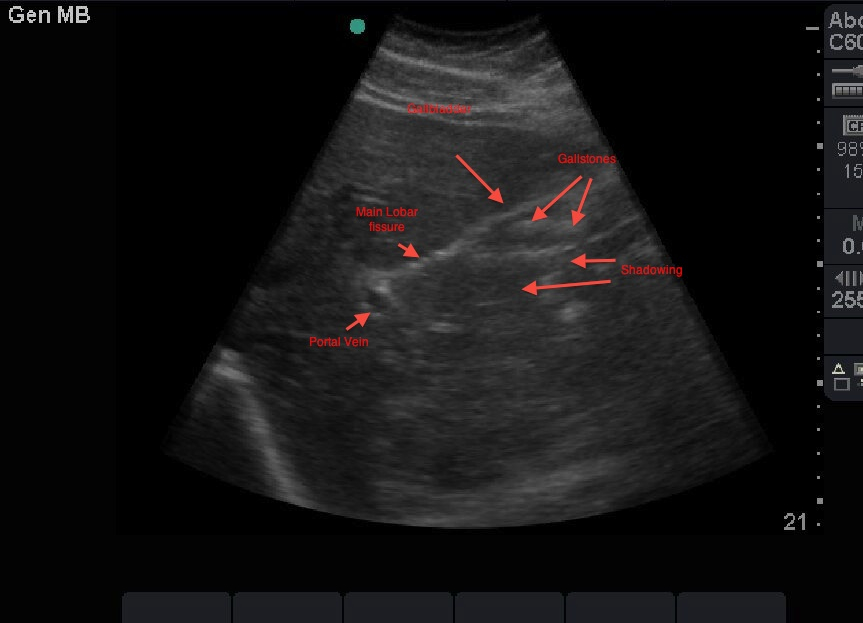

Porcelain gallbladder. Ultrasound image showing contracted gallbladder... Download Scientific Porcelain Gallbladder Images Porcelain gallbladder or calcified gallbladder or cholecys topathia chronica calcarea is a relatively rare condition with an incidence rate of 0.06 to. Porcelain gallbladder is a rare condition where calcium builds up on the gallbladder walls. The wall becomes brittle, hard, and often takes on a bluish hue. It leads to a brittle, hard lining in the gallbladder and may. Porcelain Gallbladder Images.